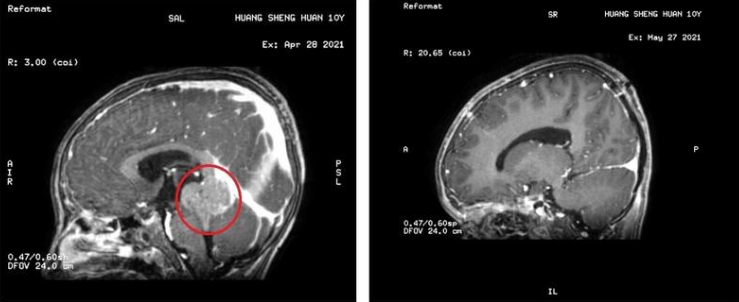

治疗前后,颅内肿瘤(红圈处)消失

方案敲定并完善相关术前检查后,4月28日为小乐进行“右侧脑室穿刺引流术”,术后小乐头晕、呕吐症状明显缓解;4月30日在全麻下进行“后正中入路第三脑室及松果体区巨大肿瘤切除术”,手术顺利完成。术后病理结果为生殖细胞瘤。目前,小乐已接受放疗和化疗,恢复良好。